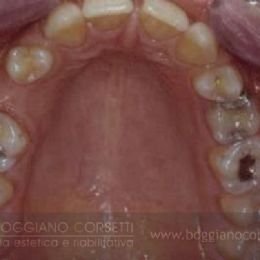

Questo è un caso in cui sono stati cambiati la posizione, la forma e le dimensioni dei denti per ottenere una proporzione più gradevole.

La prima cosa che viene subito all’attenzione è il contorno gengivale sgradevole perché il margine gengivale del laterale di sin. si è retratto in seguito ad una scorretta riabilitazione protesica.

La simmetria gengivale, la cosiddetta estetica rosa, è un parametro fondamentale da tenere in considerazione nelle riabilitazioni estetiche. Infatti, un tessuto gengivale sano, anche dal punto di vista architettonico, è un altrettanto importante fattore estetico.

Le parabole gengivali sono state corrette con il trattamento ortodontico.

mentre la forma ed il colore dei denti sono state corrette con faccette estetiche e corone in ceramica integrale con l’intervento della dr. Corsetti.

Notate come le dimensioni siano state modificate per ottenere una proporzione gradevole tra dente esposto e gengiva esposta.